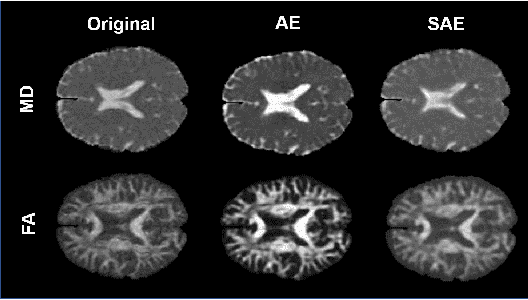

Although neural networks have proven very successful in a number of medical image analysis applications, their use remains difficult when targeting subtle tasks such as the identification of barely visible brain lesions, especially given the lack of annotated datasets. Good candidate approaches are patch-based unsupervised pipelines which have both the advantage to increase the number of input data and to capture local and fine anomaly patterns distributed in the image, while potential inconveniences are the loss of global structural information. We illustrate this trade-off on Parkinson's disease (PD) anomaly detection comparing the performance of two anomaly detection models based on a spatial auto-encoder (AE) and an adaptation of a patch-fed siamese auto-encoder (SAE). On average, the SAE model performs better, showing that patches may indeed be advantageous.